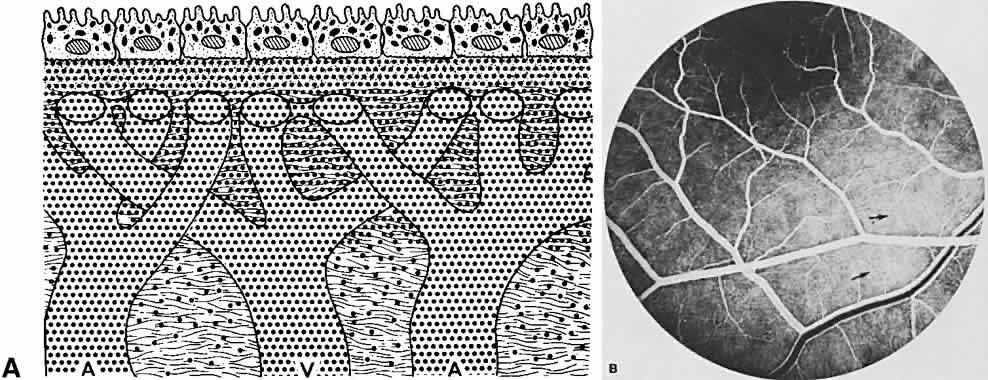

RETINA

The retina, except for its vasculature, may be regarded as a transparent tissue comprised of tightly packed layers of cells with essentially no extracellular space. The retina is perfused by the central retinal artery and cilioretinal vessels present in 32% of eyes.31 The capillary bed is nonfenestrated and fluorescein does not, therefore, leak from the retinal vessels into the surrounding tissue (Fig. 8). Functionally, the retinal vasculature represents a “closed” system, as opposed to the choroid, in which fluorescein is free to move between the intravascular and extravascular compartments. The retinal circulation normally fills with fluorescein after the choroidal flush; however, a cilioretinal artery fills at the same time as the choroid, preceding the rest of the retinal circulation.

Fig. 8. Fine structure of intraretinal capillary, showing capillary endothelium (E) and intramural pericyte (IP), both encased within a basal lamina (BL). In these capillaries there are no endothelial specializations such as the fenestrations seen in the choriocapillaris (transmission electron microscopy, × 11,200).